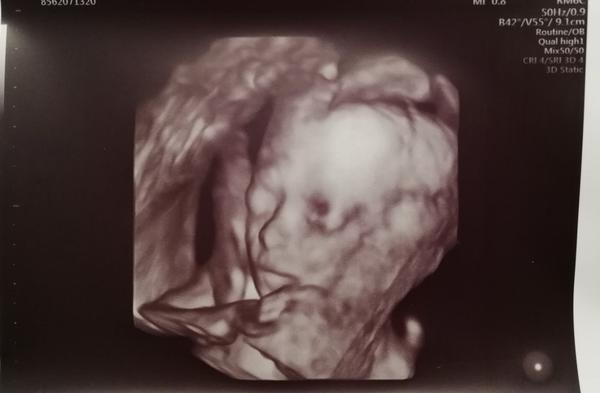

Ahoj holky, tak my máme 2. screening za sebou, byli jsme včera. Vše je v naprostém pořádku a na svém místě, vše funguje tak, jak má, opět potvrzena holčička a bylo super ji opět vidět 🙂 Pán doktor ultrazvuk přepnul na chvíli i na 3D a je to mazec vidět už ty rysy obličejíčku 🙂 Jinak my chodíme do Brna do Prenatalu, platili jsme 1200 Kč a dostali jsme 3D fotečku a nahrávku celého ultrazvuku na CD. Tak pak pisnite váš zážitek 😇

@laloogrey @1leny ahoj devcatka,moc gratuluju ke krásným zpravam,ke zdrave holčičce...ve stredu drzim palecky,urco to bude na jednicku..my jdeme v patek na 2screening a 4D video jak jsou videt i rysy jsem preobjednala az na 25tt,to jsem byla i s malou a to bylo vse videt nádherne fakt❤ tak to az 30.9..tak doufam ze konecne potvrdi pindu teda😂pac prvni genetika typ kluk a 15tt a 18tt se pletl pupecnik tak prd😂

Ahojky holky, tak u nás na druhem screeningu vsechno na jednicku🙂 Mame na 100% pindu pry🙂 tak uz tomu zacinam verit teda🙂 akorat byl celou dobu v poloze sklapovacka, nohy i ruce pred oblicejem, takze rysy smolik a jsme preobjednani na ten 25tt, tak doufam, ze to bude spolupracovat🙂 🙂